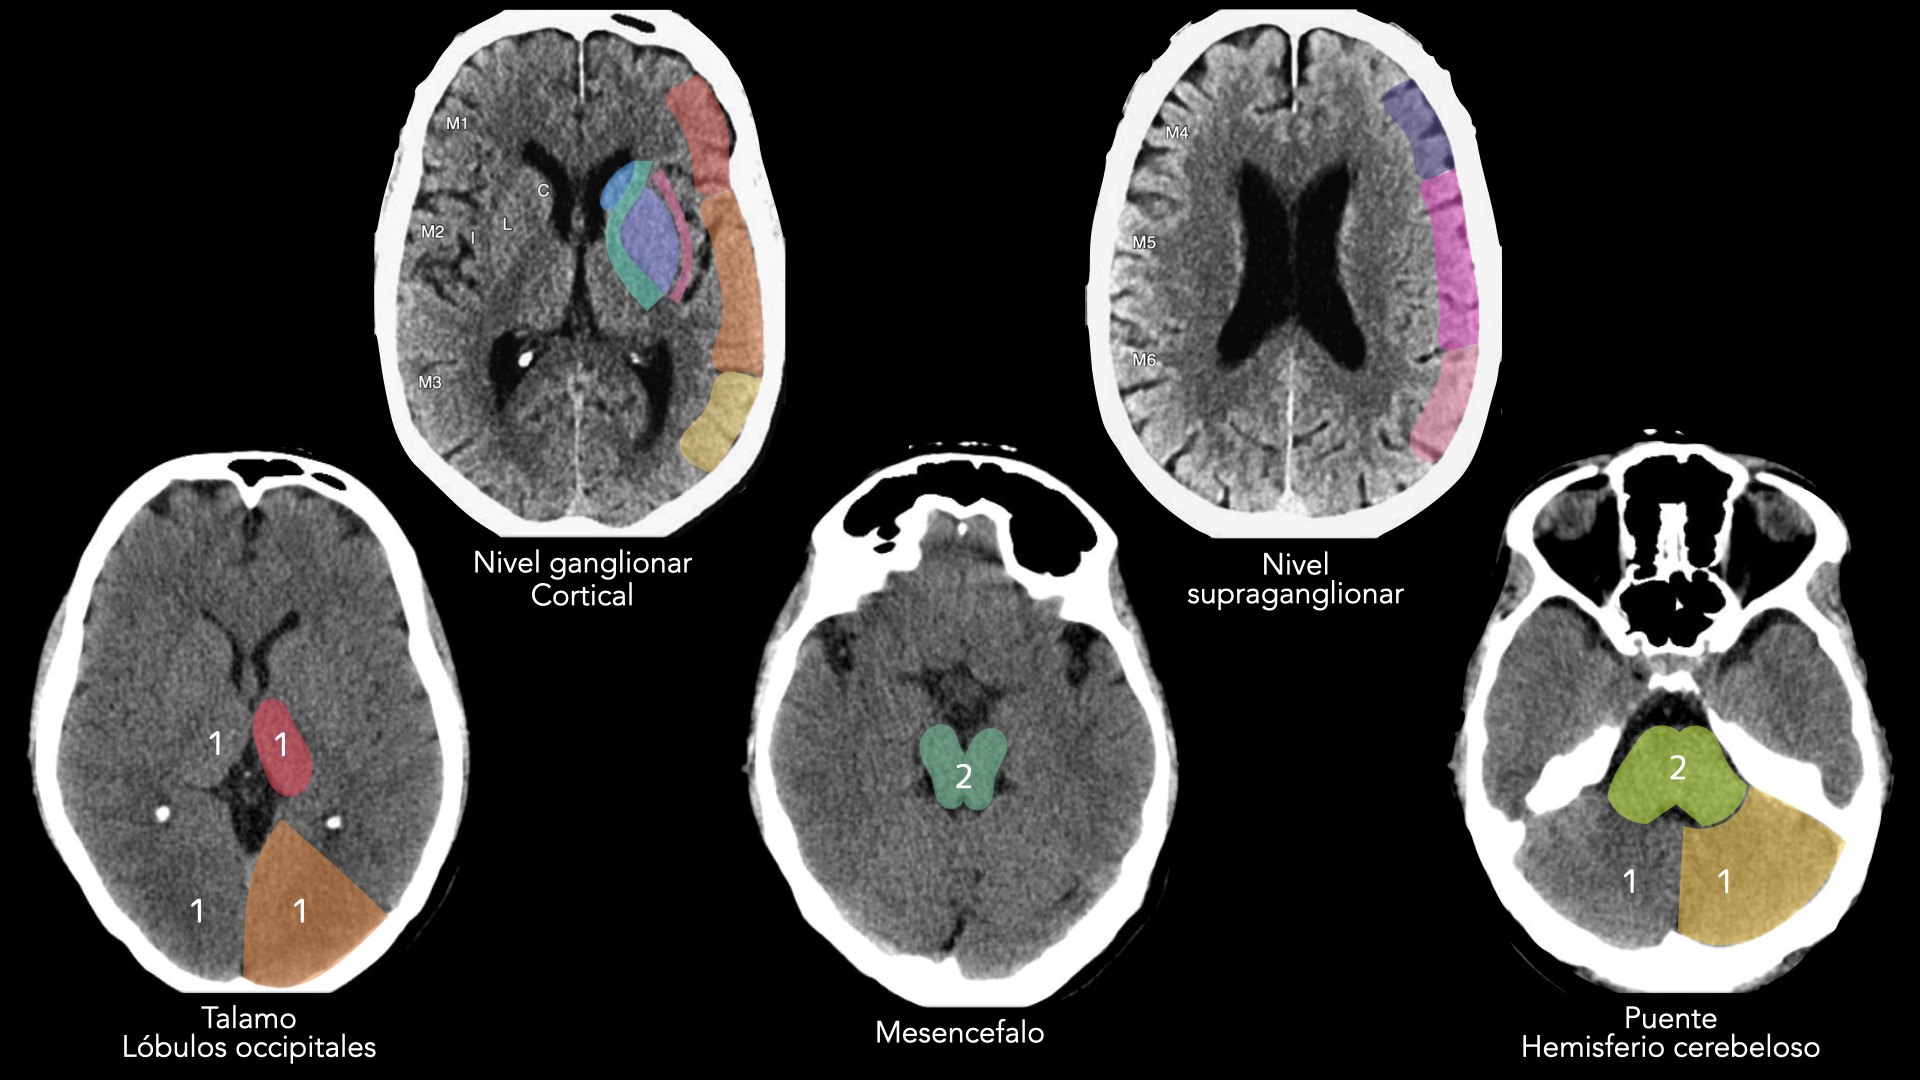

El radiólogo actúa como el “gatekeeper”. El objetivo inicial no es solo el diagnóstico, sino la selección de la terapia de reperfusión adecuada basándose en el tiempo de evolución y la exclusión de hemorragia.

• 🛑 Descartar hemorragias y simuladores (Stroke mimics).

• 🎯 Definir extensión del infarto establecido (Núcleo).

• 📍 Identificar sitio de oclusión (Terapia dirigida).

• ⚖️ Relación Núcleo / Penumbra (Viabilidad).

• 📏 Tipo, longitud del coágulo y circulación colateral.